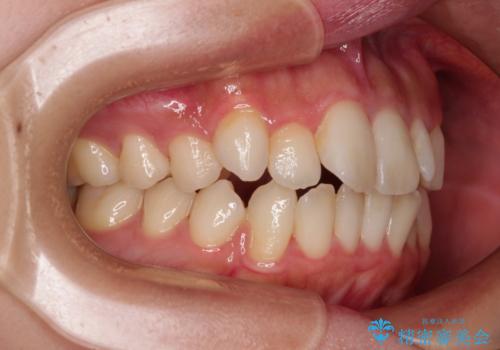

- 口元の突出感と口の閉じにくさを気にして来院された患者様です。

上下左右第一小臼歯4本を抜歯し、ワイヤー装置にて口元を引っ込めるよう矯正治療を行うこととしました。

口元の突出感が改善されてことで、下唇に引っかかっていた上顎前歯も気にならなくなりました。